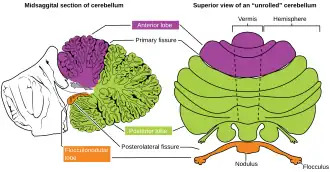

The monticulus of the cerebellum is divided by the primary fissure (or preclival fissure) into an anterior, raised part, the culmen or summit, and a posterior sloped part, the clivus; the quadrangular lobule is similarly divided.

Animation. Primary fissure shown in red.

Close up animation. Primary fissure shown in red.

Dissection video (1 min 20 s). Demonstrating the three cerebellar lobes. "V-shaped fissure" is the primary fissure.